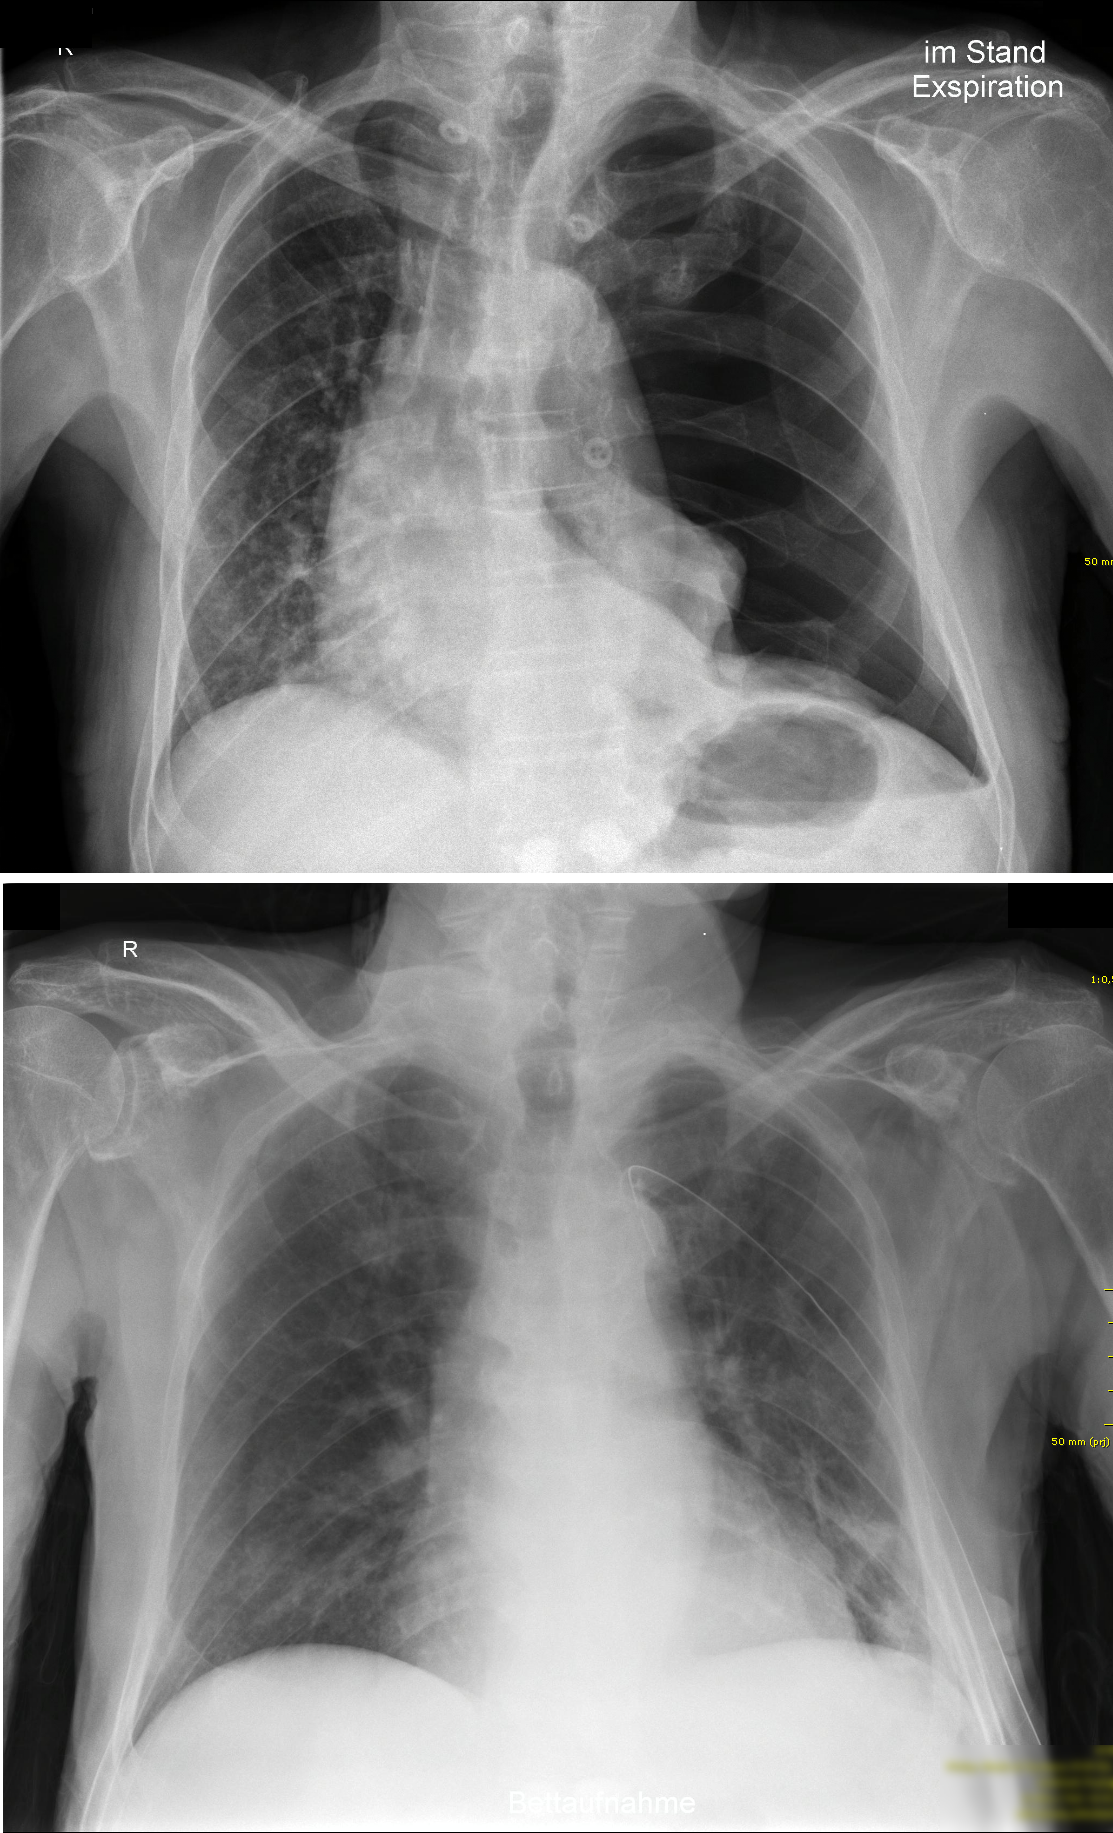

Der Pneumothorax im Lungenröntgen#

Direkte Zeichen:

• Sichtbare Pleuralinie

• Vermehrte Transparenz lateral der kollabierte Lunge

• Fehlende Gefäßzeichnung lateral der kollabierten Lunge

Indirekte Zeichen:

• Auffällig scharfe Miediastinal oder Zwerchfellkontur

• Deep Sulcus Sign

• Mediastinalverschiebung

• Hautemphysem

Zu beachten ist jedoch, dass ein (noch) kleiner Pneumothorax je nach Strahlengang unter Umständen im Röntgen keine Konturen zeigt, sich also quasi “versteckt”.

Fig. 110 Ein linksseitiger Spannungspneumothorax vor (oben) und nach (unten) Anlage einer Thoraxdrainage. Gut zu sehen ist die Verlagerung des Mediastinums hin zur gesunden Seite sowie die fehlende Strukturzeichnung im linksseitigen Pneumothorax. [© Cupr78up, ℓ CC BY-SA 3.0]#